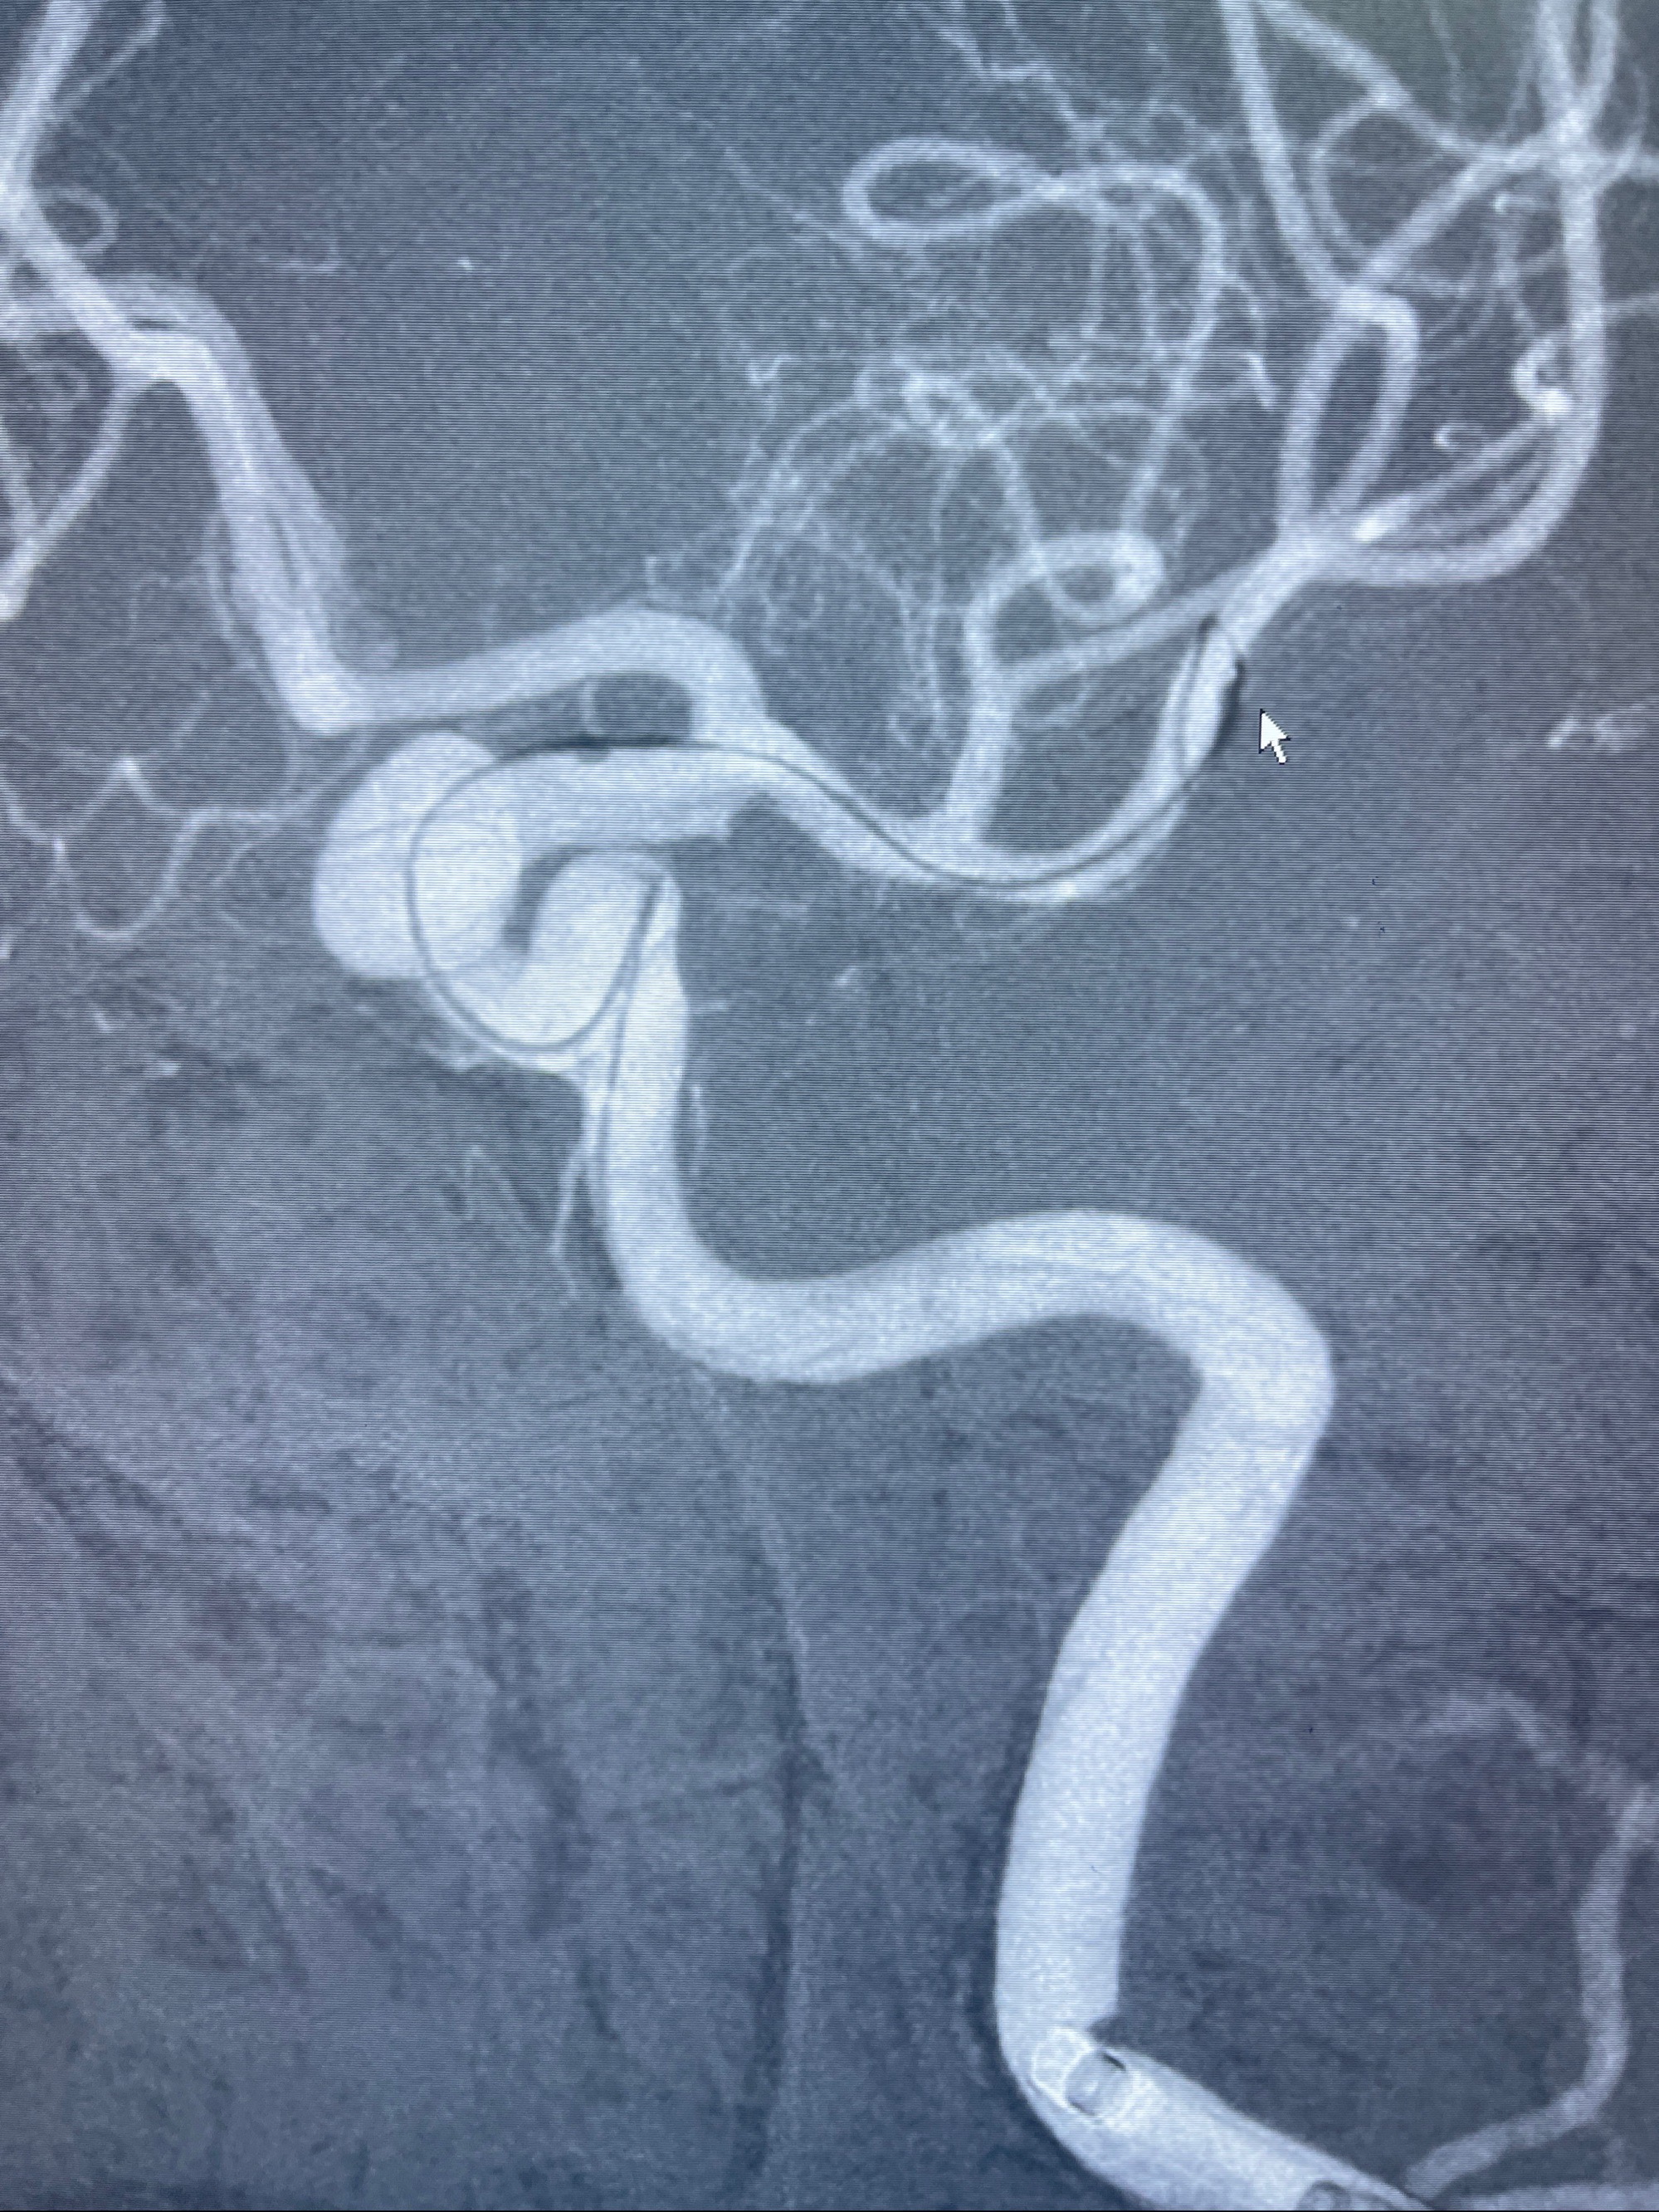

- Tubridge 4.0-20mm密网支架

术后3D显示支架贴壁佳